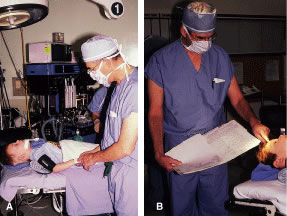

Instrument selection is reviewed by the surgeon (Fig. 1). The patient is positioned so that the head is stabilized, and a shoulder bolster or “roll” is placed under the patient's shoulders to extend the neck slightly (Fig. 2A). The patient is identified, as is the eye to receive surgery (see Fig. 2B).